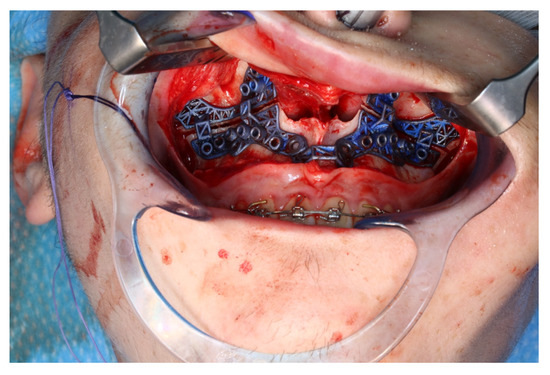

The osteotomy of the maxilla took approximately 45 min for both sides, including spot-marking of the drilling holes (Figure 9). After the osteotomy had been performed, the CARLO® device was removed, and positioning of the osteotomy lines as well as spot marking were clinically checked by superimposing the cutting guide (Figure 10). Afterwards, the osteotomy of the nasal septum, lateral nasal wall, and pterygomaxillary junction was completed using a chisel and hammer. The surgery was then completed in a conventional manner (Figure 11).

Figure 9.

Use of the CARLO® to mark the planned drill holes ((a), black arrows) as well as after drill holes were created using a conventional rotating handpiece (b).

Figure 10.

Intraoperative clinical visual control of osteotomy lines and drill holes using patient-specific cutting guide.